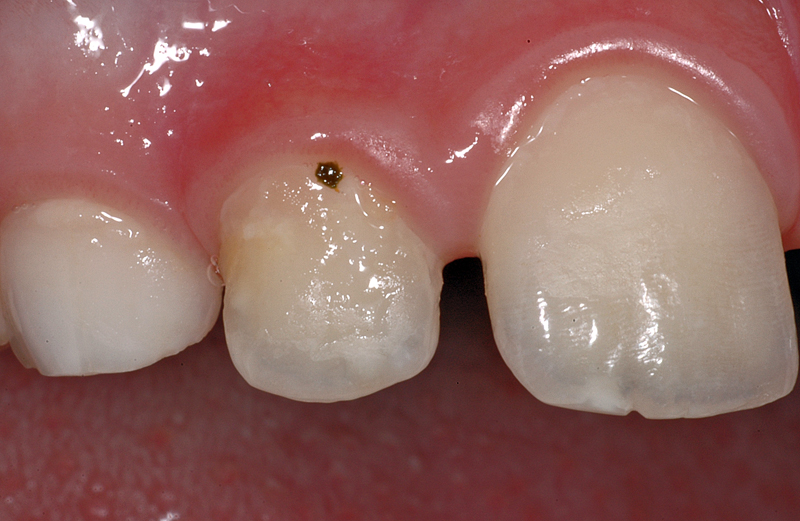

Hier ein Fall mit einem schwarz-grünlichen Fleck am Zahnfleischrand an einem oberen rechten seitlichen Schneidezahn (Zahn 22) bei einem knapp 8-jährigen Knaben.

Zudem sind noch gelblich-braune Verfärbungen im «hinteren» Teil des Zahnes zu sehen (distal).

Der dunkle Fleck ist ein Speiserest des Frühstücks (Petersilie? Origano? Thymian?) oder, auf Grund des dicken Zahnbelags (das gelblich-braune) anzunehmen, allenfalls sogar eines vergangenen Abendessens…

Mit einer handelsüblichen Zahnbürste und Zahnpaste ist das in drei Minuten behoben…

- Speiserest